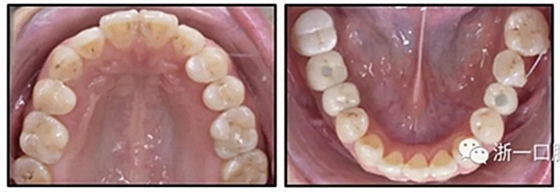

經(jīng)過32個月的活動治療后,上下牙弓排齊良好,下頜第一磨牙區(qū)的雙側牙間隙可用于種植(圖12,A和13,A)。

圖15.A,去除固定裝置一個月后,下頜左側第二前磨牙復發(fā),移動到種植體愈合的部位; B,B-0表示開始再治療,通過鏈圈和推簧的矯正復發(fā); C,B-9是治療結束后3個月回訪時下頜弓的咬合面觀,這是再治療階段的9個月。下頜左側第二前磨牙和第三磨牙的頰面粘合一個固定保持器,以防止復發(fā)。